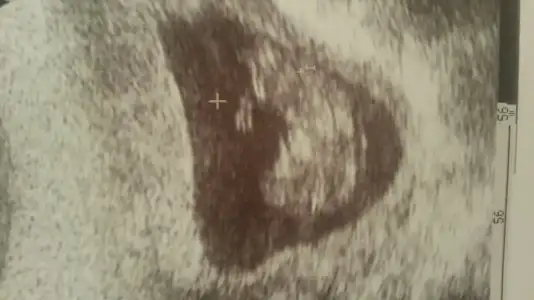

Kızlar buda bizim 12 haftalık halimix doktor göremedi çok hareketliydi sıpa haftaya belli olur dedi sizce ne :))

PrensesKızlar buda bizim 12 haftalık halimix doktor göremedi çok hareketliydi sıpa haftaya belli olur dedi sizce ne :))